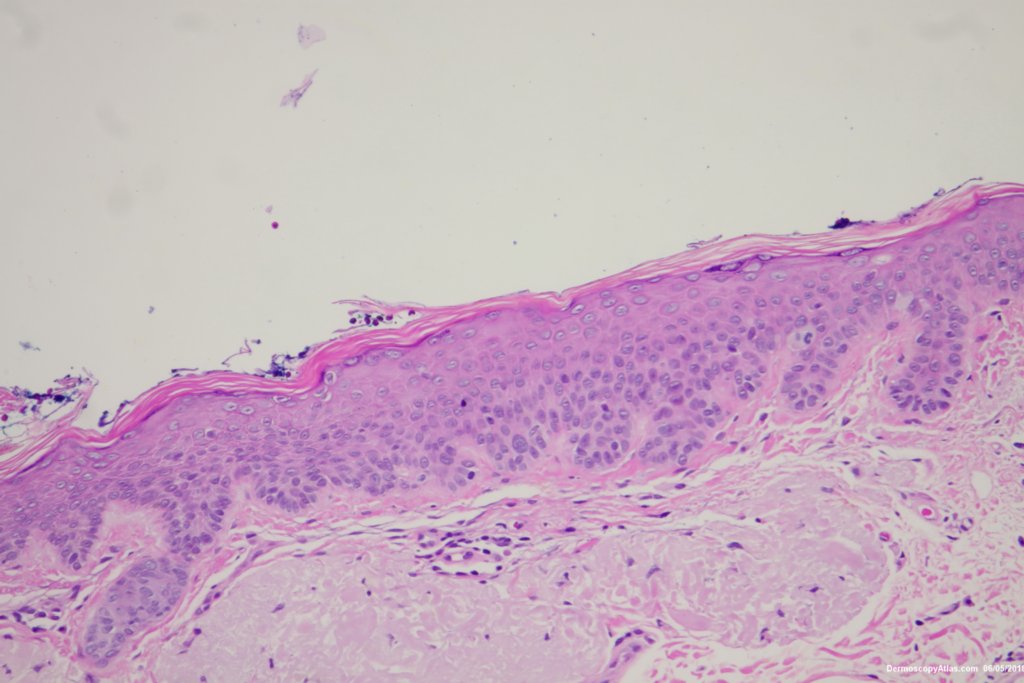

Diagnosis: Pigmented Intraepidermal carcinoma

Some pigmented lesions look melanocytic, However this is a pigmented intraepidermal carcinoma. Some areas show more full thickness atypia than others. The dermatoscopy shows some dots in rows but there are other grey dots showing regression at one edge.